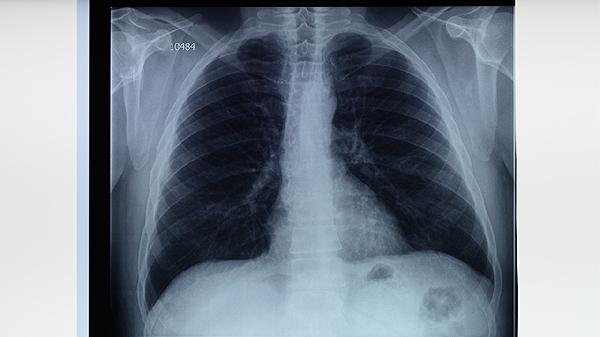

肺结核是由结核分枝杆菌引起的慢性传染病,标准治疗方案分为强化期和巩固期。强化期通常为2个月,需联合使用异烟肼片、利福平胶囊、吡嗪酰胺片和乙胺丁醇片四种药物,快速杀灭活跃菌群。巩固期持续4-7个月,主要使用异烟肼片和利福平胶囊清除残留菌群。服药五十天尚处于强化期阶段,此时体内细菌尚未完全清除,若擅自停药可能导致细菌复燃或产生耐药性。耐药结核病治疗周期将延长至18-24个月,且需使用二线药物,治疗难度和费用显著增加。

极少数情况下,医生可能根据痰菌转阴情况、影像学改善及药物不良反应调整方案,但必须由专科医生评估决定。对于出现严重药物过敏或肝功能损害的患者,需在医生监督下更换药物而非直接停药。治疗期间应定期复查痰涂片、胸部CT和肝功能,确保疗效与用药安全。